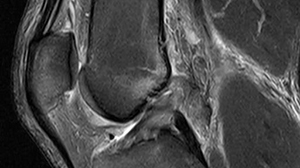

The anterior cruciate ligament (ACL) is a ligament that runs diagonally through the inside of the knee. It connects the underside of the femur (thigh bone) to the top of the tibia (shin bone). The ACL prevents the tibia from moving in front of the femur and gives the knee joint stability; it also helps control the backwards and forwards movement of the knee.

Immediately after the rupture, you are advised to rest, ice, compress and elevate (‘RICE’) the joint. MRI scans are performed to confirm the diagnosis and to see if other damage to the knee joint has occurred.